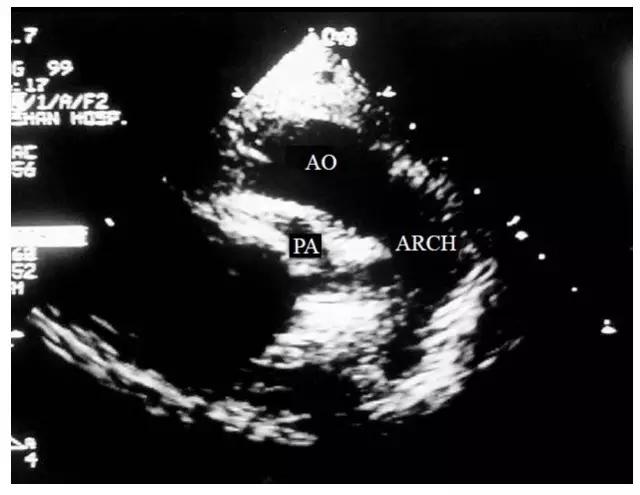

为了分辨主动脉和肺动脉,可进一步取胸骨旁左心室矢状切面,沿升主动脉向上追踪两根大动脉的走行,两根大动脉并行上升一段短距离后,后位的血管内径较细并首先分叉,此为肺动脉;而前位的血管内径较粗并继续向上行走,此时将探头方向指向脊柱左前方及左侧,即可显示它向后方弯曲,并弯成弓状,此为主动脉(图10-4-4),这种图像有时在剑突下右心室流出道长轴切面也能看到。根据以上这些特点可初步区别两根大动脉。

图10-4-4 大动脉转位的胸骨旁左心室矢状切面

沿升主动脉向上追踪两根大动脉的走行,见前位较粗的血管向后方弯曲,并弯成弓状,此为主动脉(AO-主动脉 ARCH-主动脉弓 PA-肺动脉)